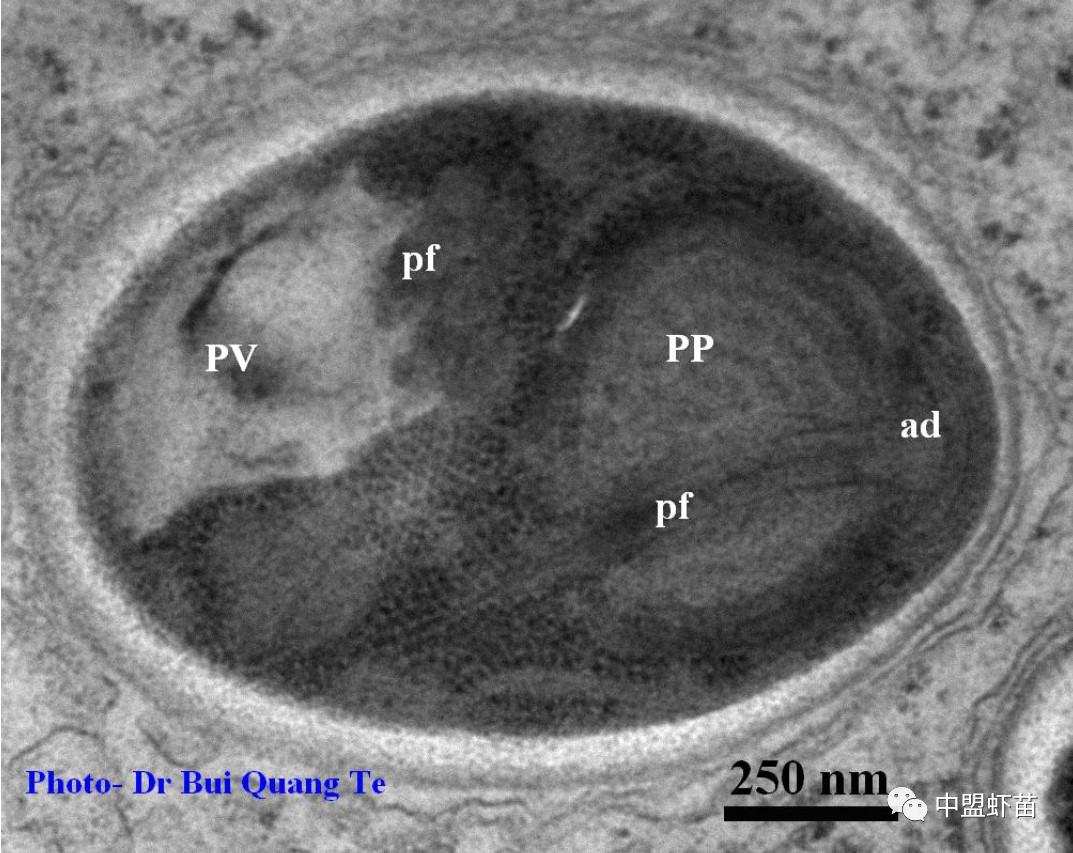

成人孢子电子显微镜垂直切成椭圆形,尺寸为0.60 x 1.86μm,前面有囊性极(PP),前端为粘附盘(ad),后面有液泡(PV),中间有1个核(N),上两侧有细丝 (pf)(图10-11)。 孢子阶段在宿主细胞质(肝胰腺细胞)中发育,宿主细胞表面含有许多小颗粒(泡)。

图11:孢子切椭圆形,正面有有囊性极(PP),前端有附着盘(ad),后面有液泡(PV),中间有1个核(N),两侧杆有细丝 (pf)。